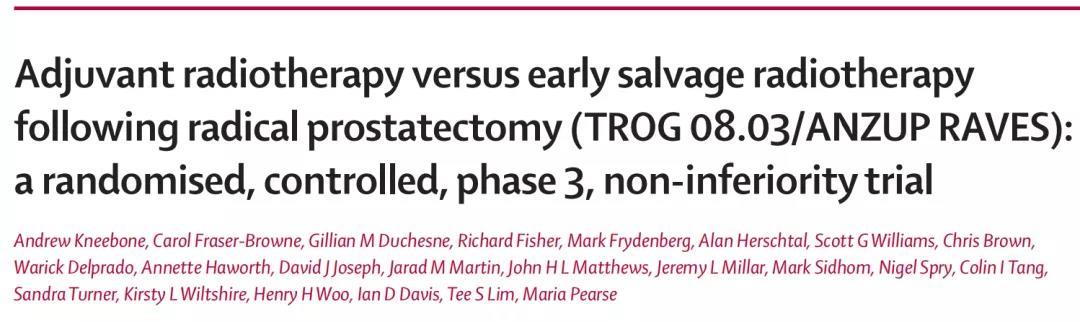

对于合并高危病理因素的前列腺癌患者,根治术后进行辅助放疗一直是美国ASTRO等权威组织推荐的标准方案,但在具体临床实践中,术后密切观察必要时行早期挽救放疗的做法也...